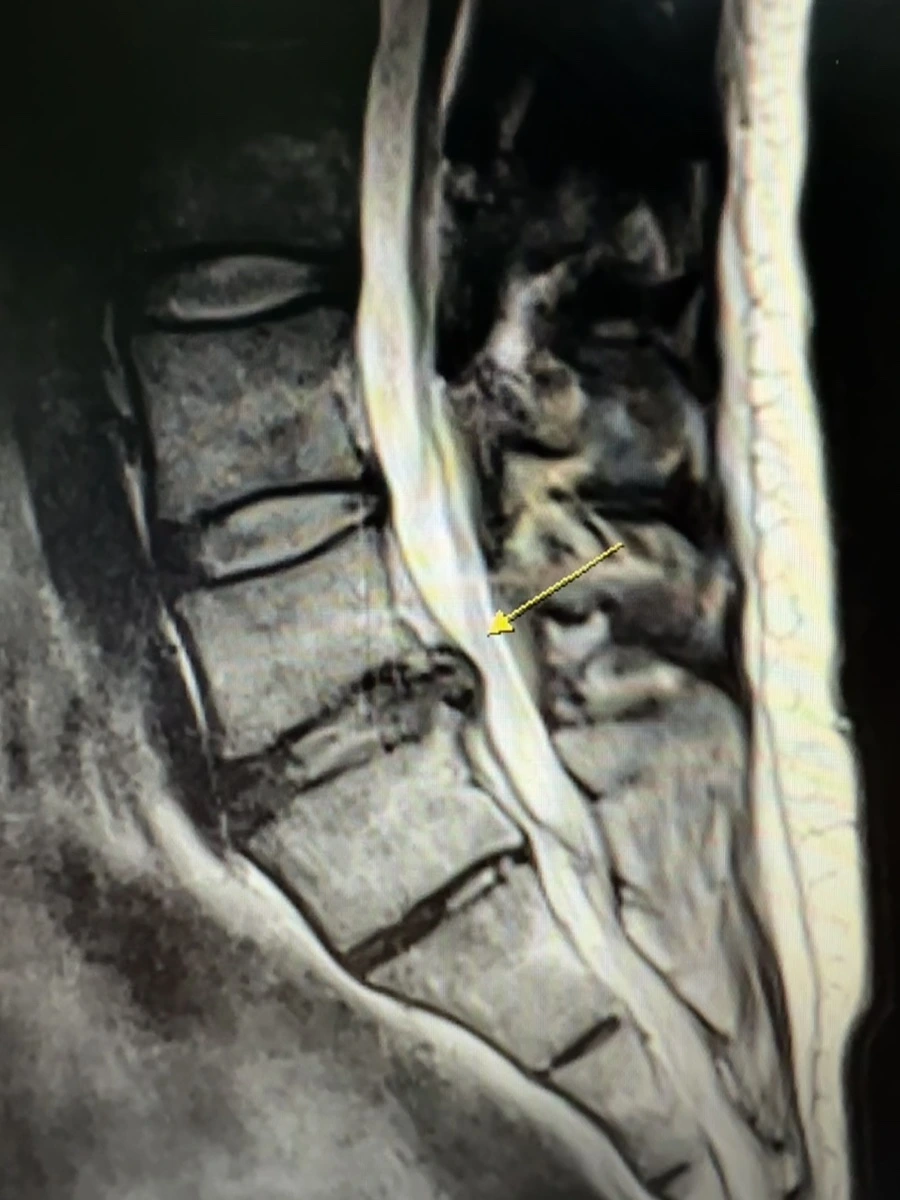

교통사고 후 허리 디스크가 심해져 결국 MRI 의뢰서를 받고 MRI를 찍었다.

디스크 수액이 튀어나와 있었고 의사가 MRI를 보더니 이건 교통사고 때문이 아니라 원래 가지고 있던 디스크로 보인다는 소견을 말하자 역시 의사는 의사라는 생각이 들었다.

최근 많이 낫고 있어서 걸을 때 통증도 거의 없어졌었는데 사고 후 다시 통증이 재발해 스트레스를 받고 있다.